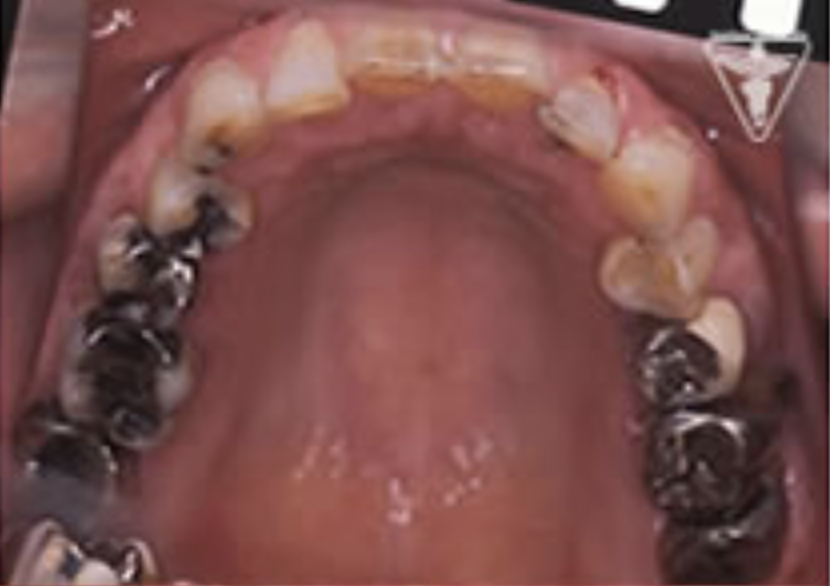

治療前

下の奥歯が左右なくなっており、かみ合わせが深くなっています。

顎のずれは認めませんが、歯肉が厚く中に炎症を取りこみやすいタイプの歯肉です。